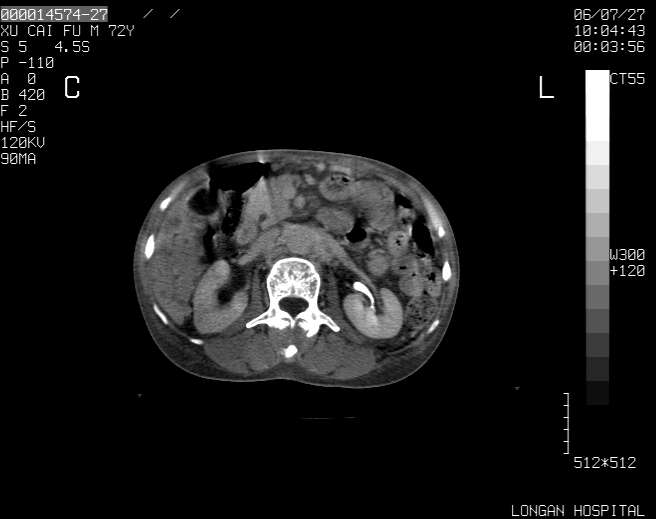

以下是引用winter在2006-7-30 20:14:00的发言:[br]1、考虑胆囊癌伴胆道侵犯并高位胆道梗阻、肝内多发转移、腹膜后淋巴结转移。[br]2、右肾轻度积水。[br]3、老人家72岁了胰腺头体尾部均较饱满,不过未见密度异常及其他异常征象。[br]4、腹水。

以下是引用jiajie在2006-7-31 7:10:00的发言:[br]考虑肝转移瘤,腹膜后淋巴结增大。[br]胃癌不能除外,建议胃镜检查。